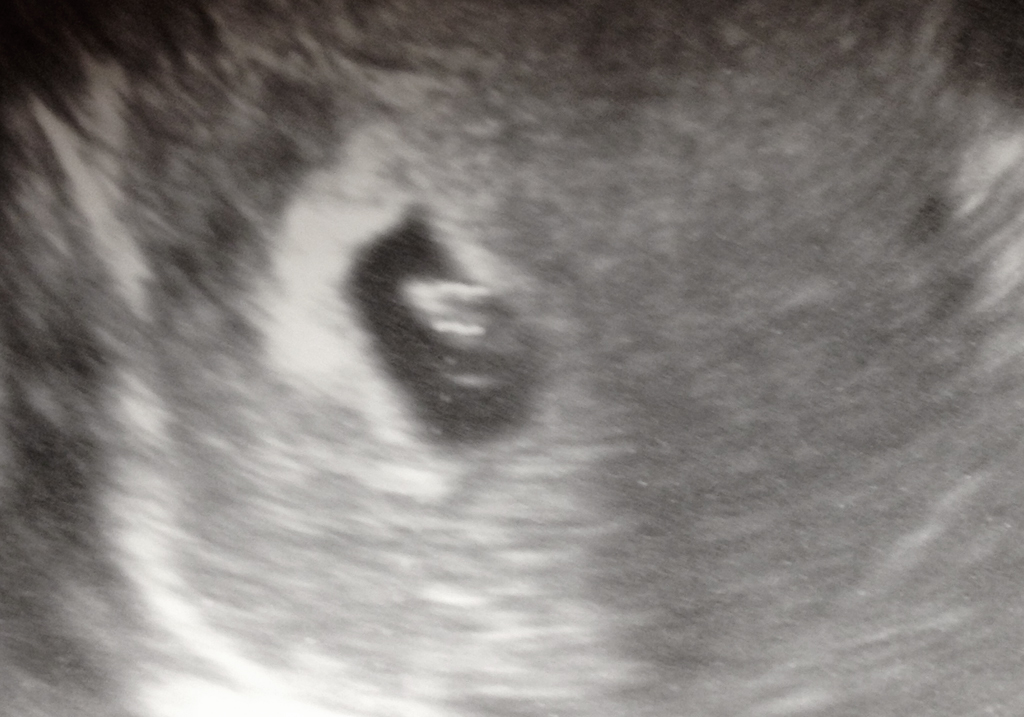

But almost instantly after the doctor began performing the ultrasound, you appeared before our eyes! And then we heard (and saw) your tiny little heart beat! The doctor seemed almost as happy as we were and reassured us that you were looking good. We will get to take another peek at you next Monday, hopefully you’re learning quickly to not be shy. Anyhow little one, for your mom and me, you were the best anniversary gift ever.